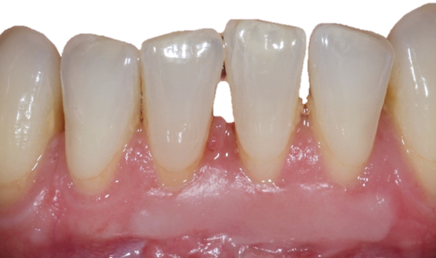

![]() | ![]() |

| Free gingival graft surgery’ to thicken gum and prevent further recession | Gum recession surgery in an aesthetic site |